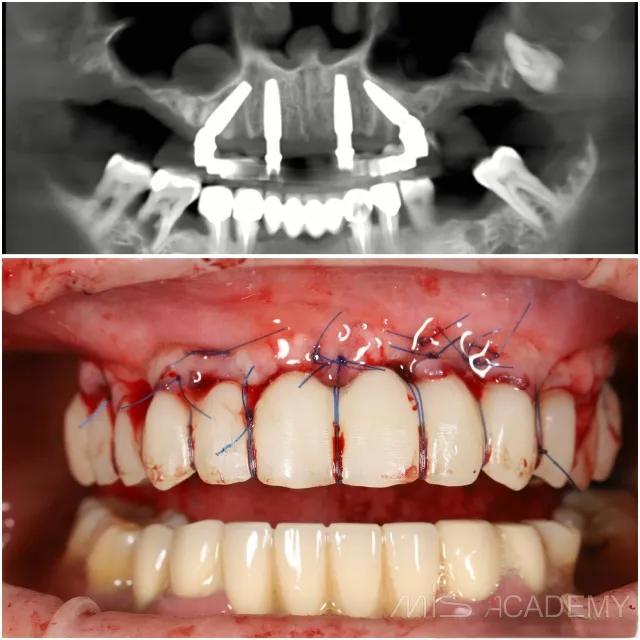

Удаление зубов на верхней челюсти

— Установка имплантатов по концепции all-on-4.

— Mis Implants MIS C1.

— Установка двух connect abatement, двух multi-unit 30 градусов.

— Внутриротовая сварка.

— Двойные обвивные швы.